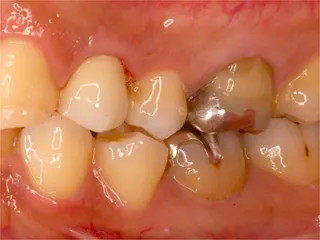

セラミックインレー(自費)・治療前・樹脂製の詰め物が割れて浮いています 治療前

セラミックインレー(自費)・治療後・ピタリと適合し色も自然に仕上がっています 治療後

プラスチックが破折したため審美的なセラミックインレー(左上小臼歯:○部分)を入れました

セラミックインレーは特殊な陶器で 歯と強度を近く作ってあるため高い耐久性があります 色を歯に合わせることも可能です